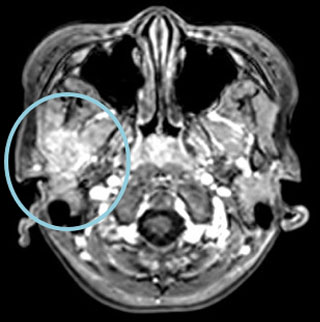

右下顎骨にLCHの骨再発をきたした。HU内服治療を開始後、溶骨部分の順調な修復が認められた。

MRI T1造影

2か月後